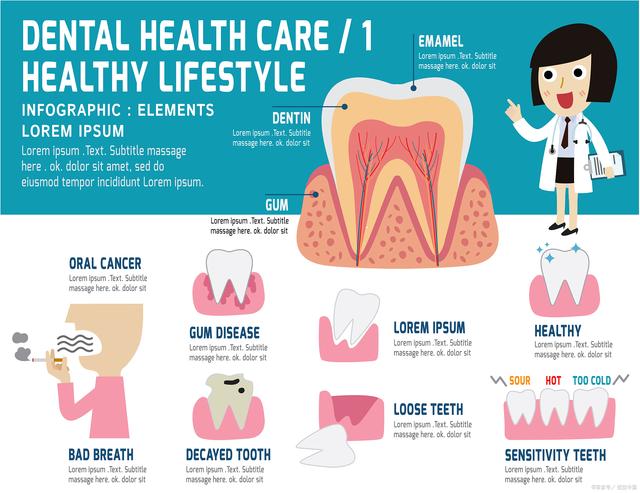

口腔健康是指口腔内部的牙齿、牙龈、舌头、唇腭、口腔黏膜等组织结构的健康状况,包括牙齿的完整性、牙龈的健康、口腔黏膜的正常状态等。同时,口腔健康还与口腔内微生物的平衡、口气的清新度等方面有关。

口腔健康的影响因素很多,包括遗传因素、饮食习惯、生活习惯、口腔卫生等。其中,口腔卫生是最重要的因素之一,不良的口腔卫生习惯会导致牙齿龋齿、牙周病等口腔疾病的发生。

牙周病是由于牙周组织受到细菌感染而引起的一系列疾病,包括牙龈炎、牙周炎和牙周组织萎缩等。预防牙周病的方法包括:

牙齿敏感是指牙齿在刺激下出现疼痛或不适的症状,主要由于牙齿表面的牙釉质磨损或龋齿等问题所导致。预防牙齿敏感的方法包括:

只有牙齿健康才算口腔健康

口腔健康不仅仅是牙齿健康,还包括牙龈、口腔黏膜、舌头等组织结构的健康状况。只有综合考虑口腔内各个方面的健康状况,才能真正实现口腔健康。